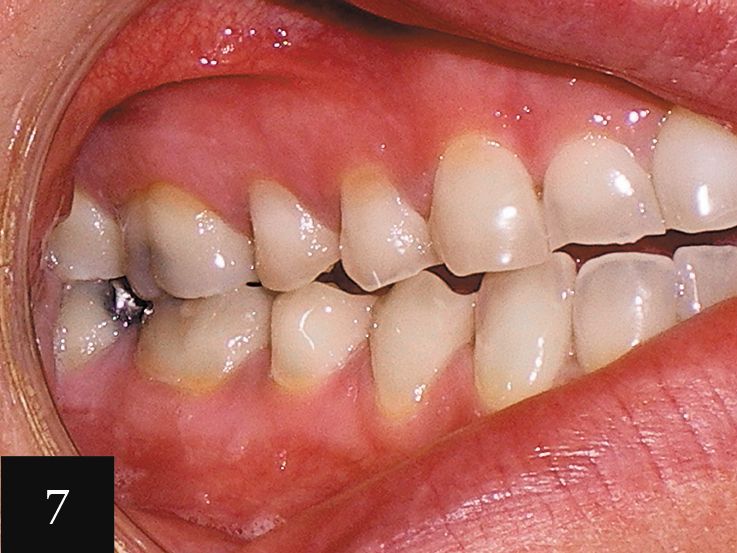

Case No. 2

This case showcases a woman in her mid-30s who had an anterior open bite, as well as a history of bulimia (Figs. 5-6). The eating disorder led to severe wear, which can be seen on the upper arch. The gum line was also very irregular. The impression accurately captured the detail of the teeth and a series of 12 aligners was made.

Following this initial phase, an additional impression was taken for six more aligners. Finally, one more impression was taken with Imprint 3 VPS impression material to create crowns for tooth Nos. 3-14. This treatment significantly elevated the patient’s level of confidence in her smile (Figs. 7 and 8).